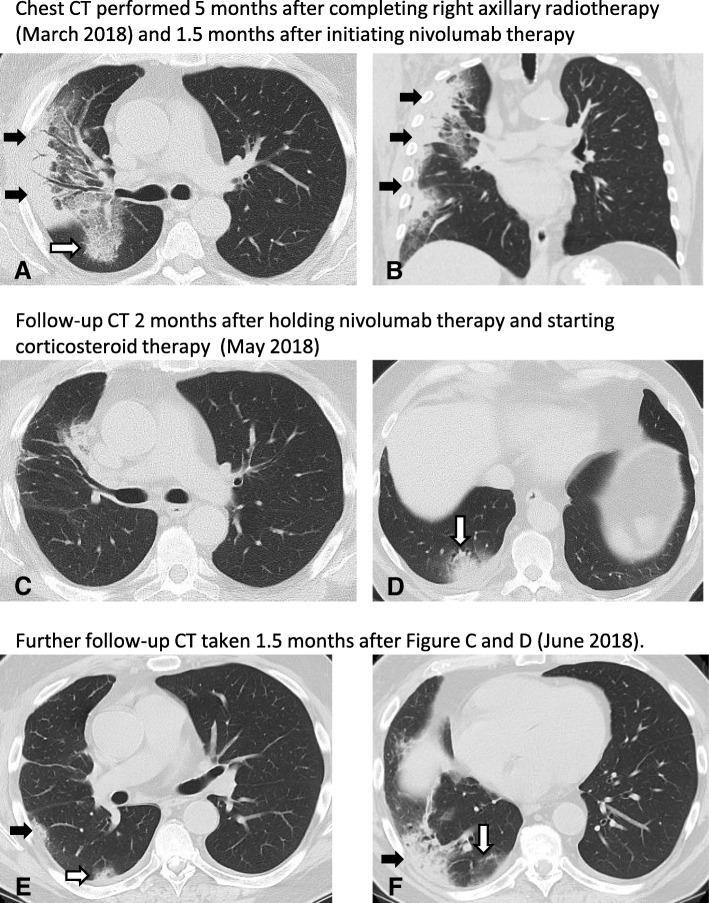

CASE PRESENTATION

We report longitudinal clinical and radiologic data, and circulating biomarkers in a melanoma patient treated with axillary radiation followed by ICB who developed consolidation and ground glass opacities (GGO) within the radiation field suggestive of radiation-pneumonitis followed by consolidation outside of the radiation field suggestive of ICB-related pneumonitis. Of note, symptomatic radiation-pneumonitis developed despite a low radiation dose to the lung (V20 < 8%), and ICB-related pneumonitis was limited to the ipsilateral lung, suggesting additive effect of radiation and ICB in the development of lung injury. Circulating biomarker analyses demonstrated increases in CXCR2, IL1ra and IL2ra that coincided with the development of symptomatic pneumonitis.

CONCLUSIONS

These data highlight the imaging findings associated with radiation and ICB-related lung toxicity, and anecdotally describe a clinical course with circulating biomarker correlates. This information can help guide clinical evaluation and future research investigations into the toxicity of combined radiation immunotherapy approaches.